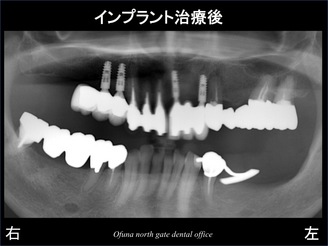

以下が治療後のレントゲン写真です。

ちなみに この症例で使用したインプラントは、アンキロス インプラント です。

昨年から 前歯部等の審美的な部位では、このアンキロス インプラント を使用する頻度が高くなりました。

非常に優れていると感じています。